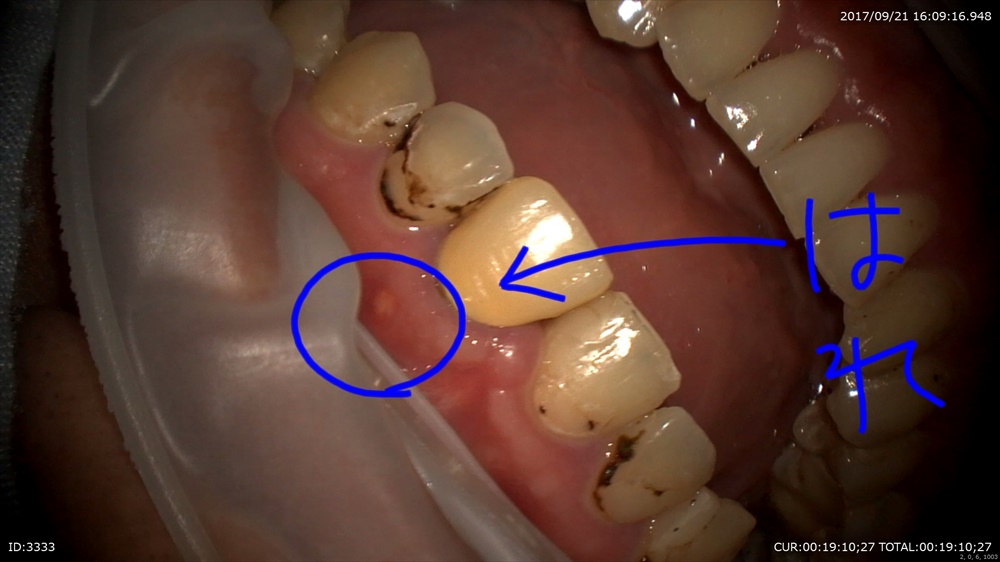

最後は精密根管治療 11月。はこの方重症のむし歯で歯茎がはれてます。

本日 きえたー。嬉しい!

比較